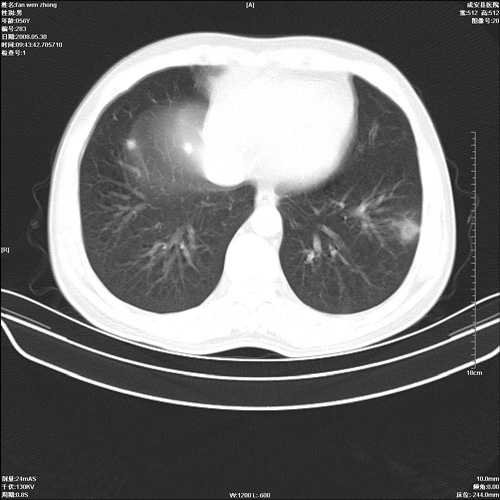

病人 男 56岁 一周前高热,体温达39-40度,经抗炎治疗后,体温渐降,达37,5-38度,轻微咳嗽,胸部不适 查白细胞为1.3万 行ct检查,请分析。

该病例虽然血象高,一周前高热。警惕!不能除外右肺周围型肺癌并肺内转移。一定要作胸穿、病理检查,以便确诊。或继续抗炎治疗后复查ct。

双肺内可见多发结节状病灶,并见小空洞,病人高热,白血球增高,应该是典型的迁徙性肺脓肿(多为金黄色葡萄球菌感染)。查一下口腔等其它部位有无感染灶。

双肺内可见多发结节状病灶,并见小空洞,病人高热,白血球增高,应该是典型的迁徙性肺脓肿(多为金黄色葡萄球菌感染)。建议治疗后复查.